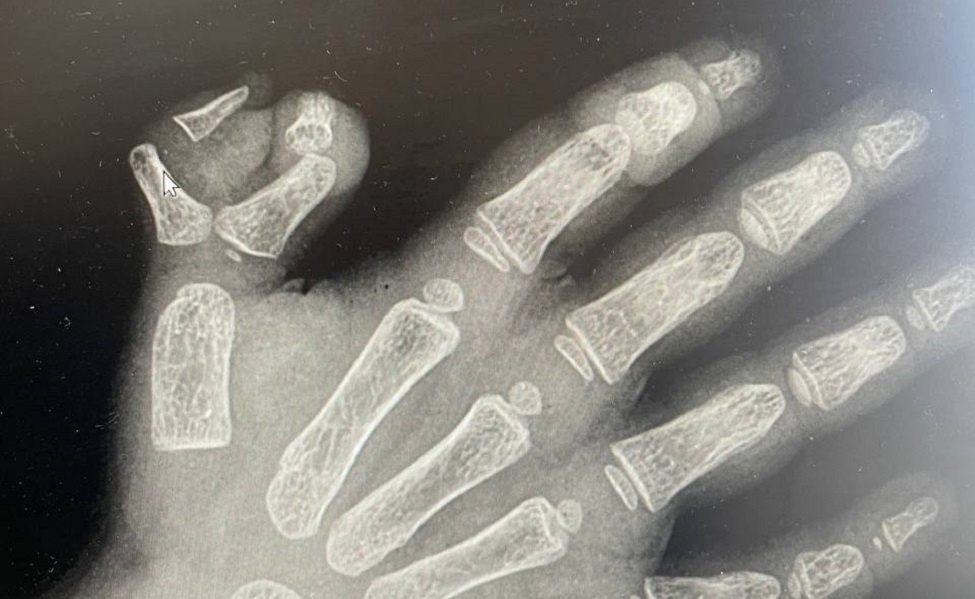

Маленькая ельчанка страдала полидактилией правой кисти с рождения. У девочки на ручке было шесть пальцев. Ребенку-правше было тяжело работать рукой (брать игрушки, столовые приборы и так далее). Полидактилия усложняла девочке жизнь.

В Ельце травматологи городской детской больницы провели успешную операцию по удалению шестого пальчика на руке у двухлетней девочки. Об этом сообщили в министерстве здравоохранения Липецкой области.